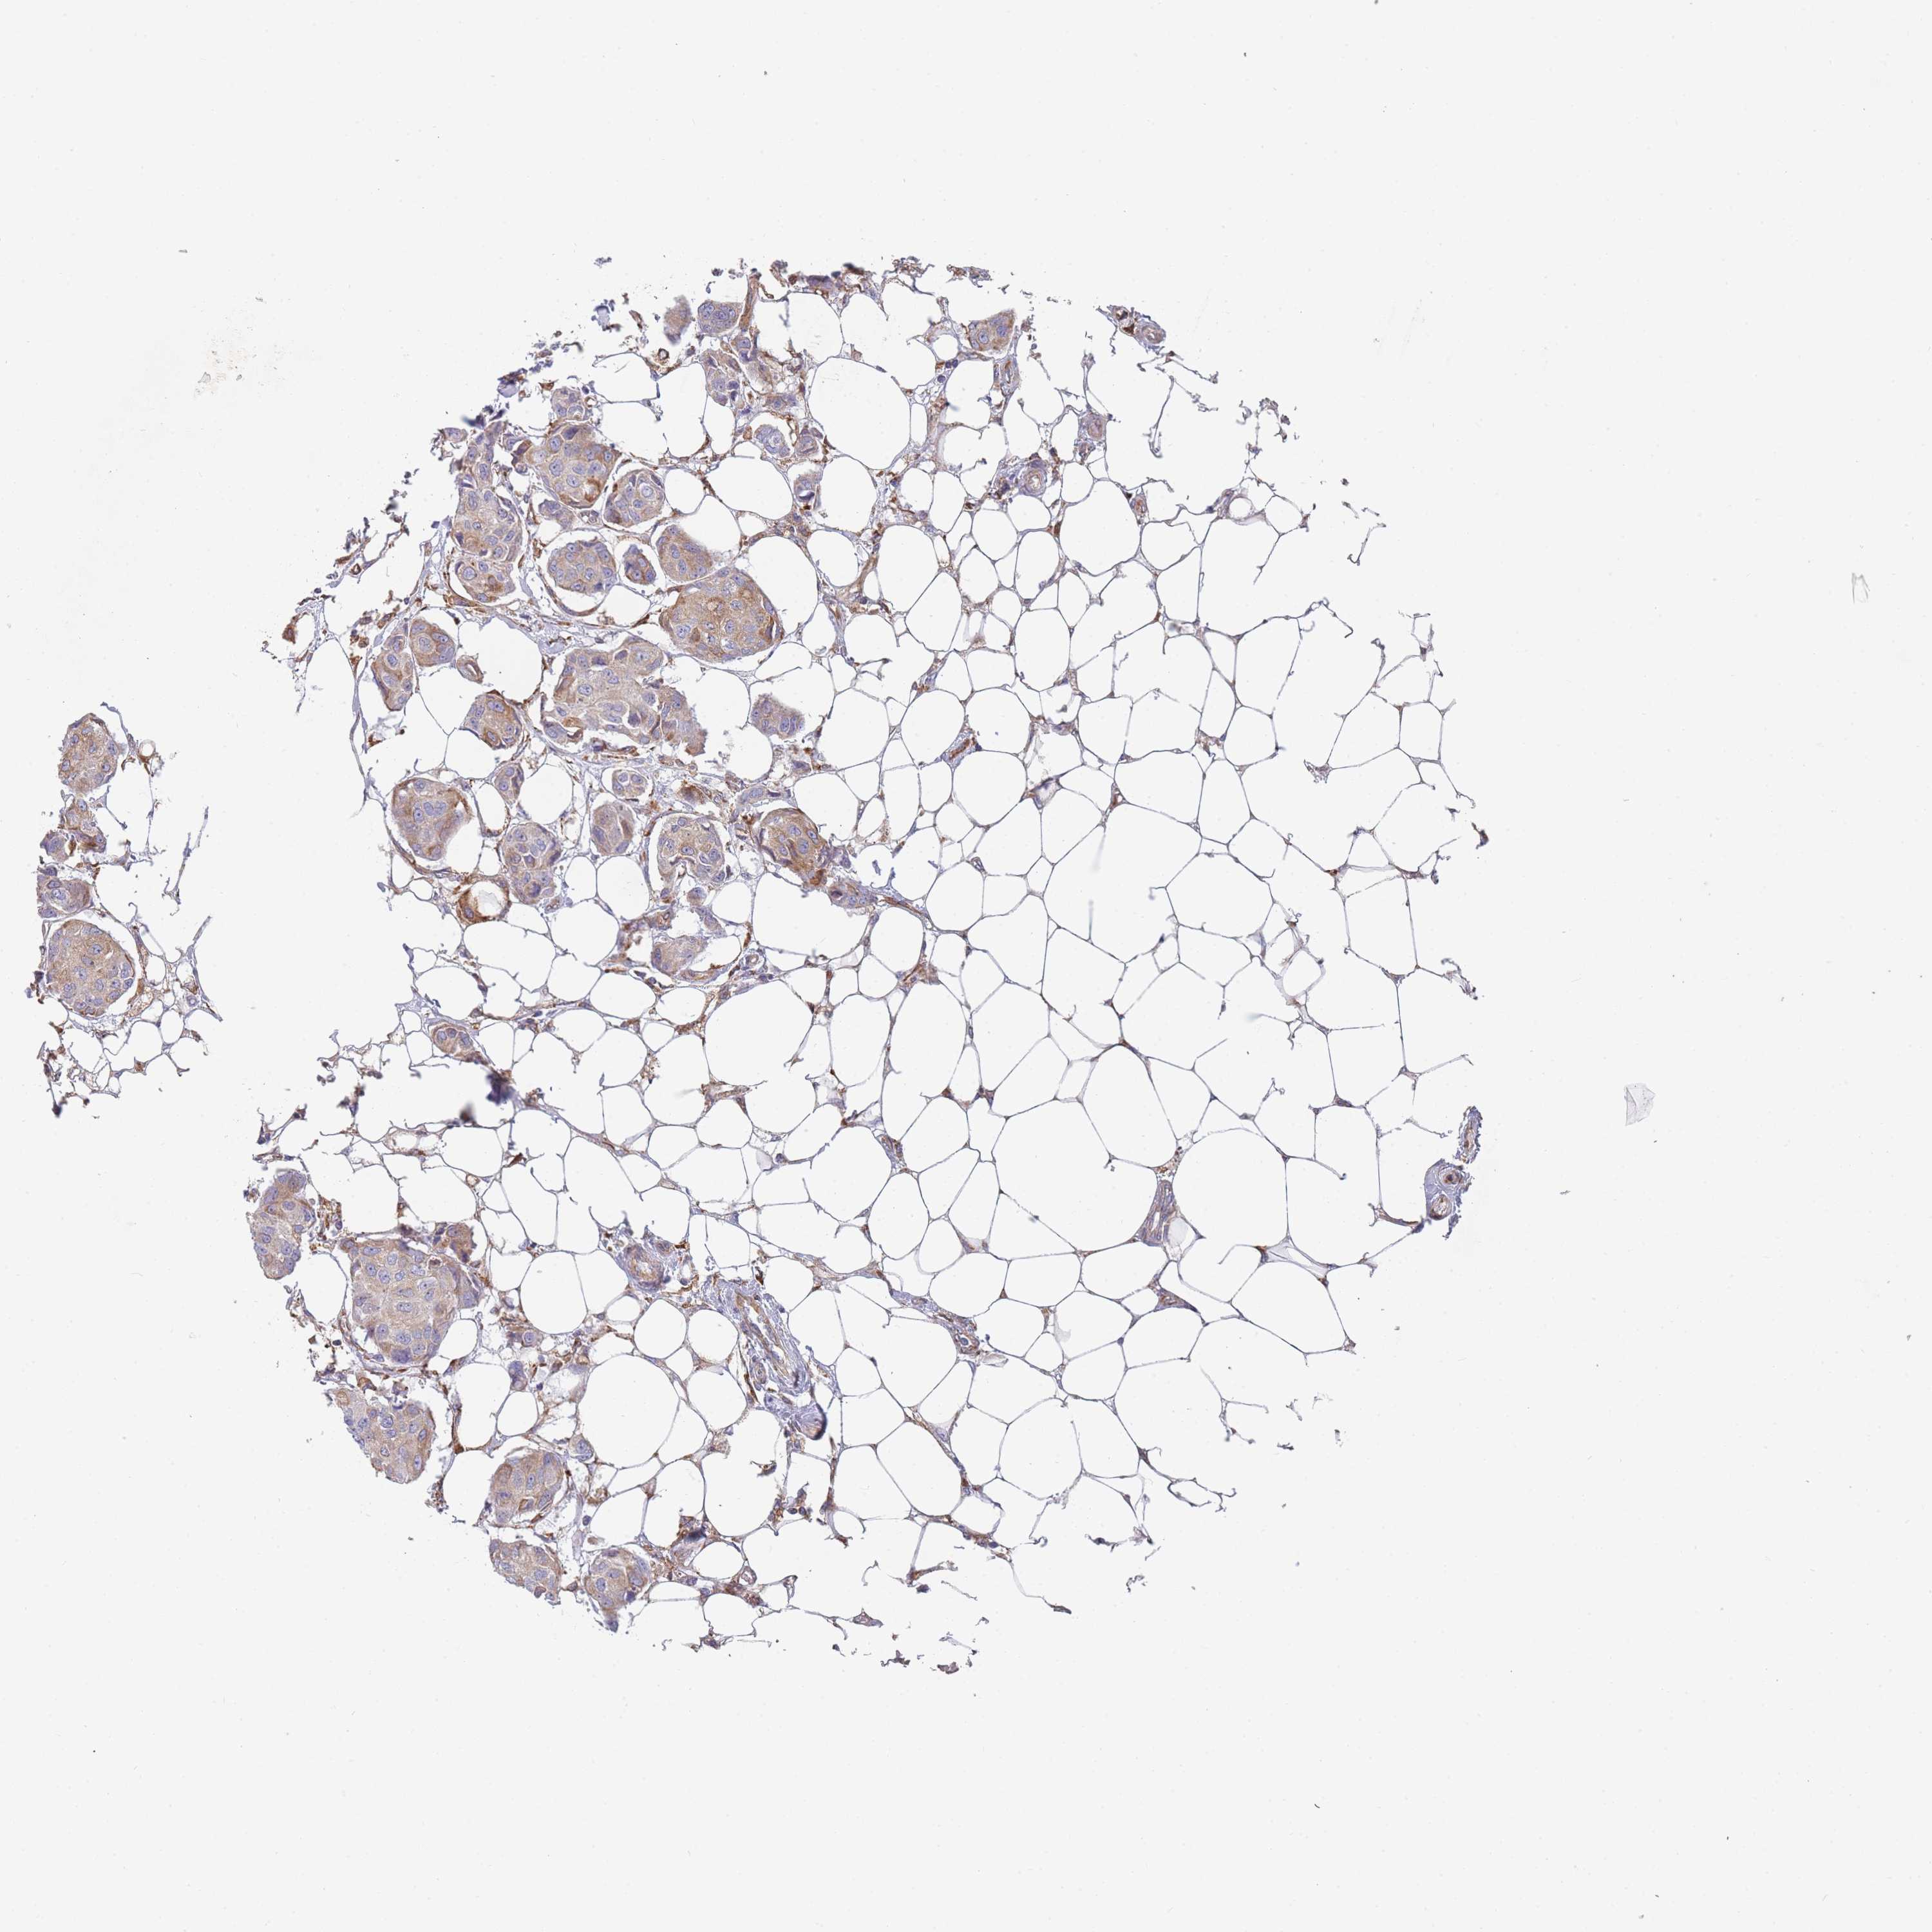

CANCER BREAST CANCER Show tissue menu

Breast cancer

Human cancer